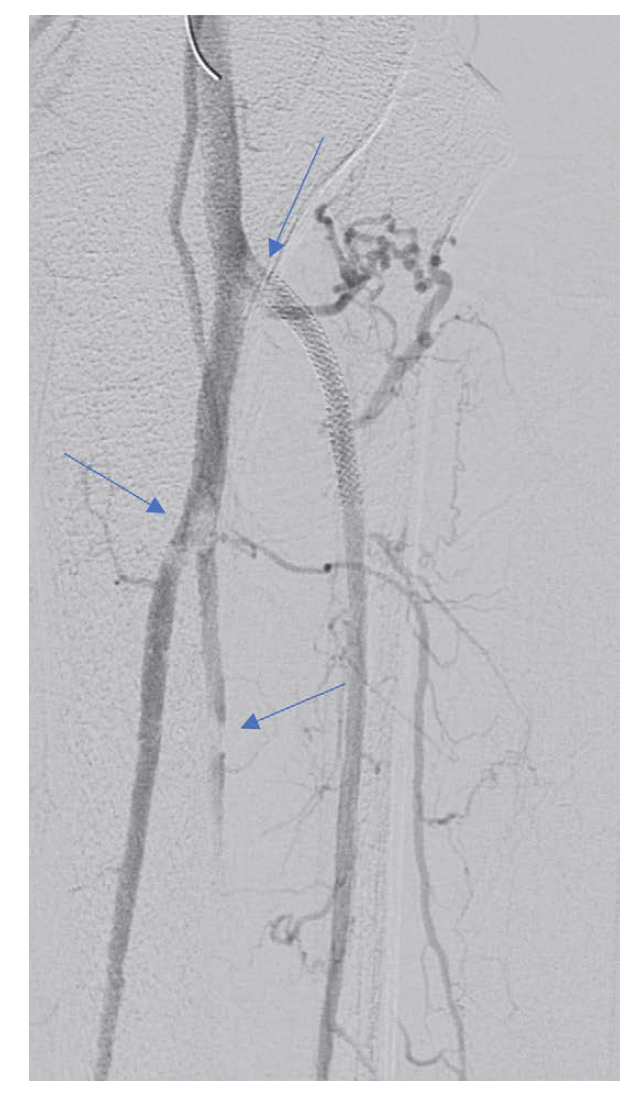

While access sites constitute the most common type of procedural complication, vessel rupture is the most feared complication and can occur at any vascular level. Rupture of an iliac artery can result in precipitous and catastrophic hemodynamic compromise if not immediately treated (Figure 2). I keep a number of covered stents on the shelf to mitigate this complication, should it occur. These stents include both balloon-expandable and self-expanding varieties of varying sizes. Many of these stents will outdate on the shelf, and I will replace them. I also keep embolization coils in inventory, as these coils can be helpful for small vessel perforation or vessel “leaks.” Stocking devices is a form of insurance that will hopefully not need to be used.

The rare occasions of iliac rupture are typically cases of chronic total occlusion (CTO) recanalization with subintimal wire passage. Therefore, in cases of iliac artery CTO recanalization, upsize the sheath prior to balloon dilatation so that precious time is not wasted performing this maneuver if a rupture occurs. Intravascular ultrasound can also be used prior to aggressive balloon dilatation or stenting. In all cases, it is important to recognize the potential complications for each case and to be appropriately prepared. For some of us, this knowledge unfortunately comes from personal experience, but much can be gleaned from presentations at the “Worst Complications” session at most conferences. Everyone can benefit from attending these types of sessions.